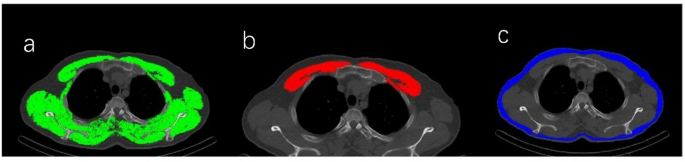

Based on established evidence of the strong correlation between body composition and stature, this study utilized CT components from SPECT/CT examinations to perform body composition measurements. Analyses were conducted on a single axial slice at the level of the fourth thoracic vertebra (T4) using Slice-O-Matic software (version 5.0; Tomo Vision, Montreal, Canada) (Figure. 2). Tissue segmentation was performed based on Hounsfield Unit (HU) thresholds: skeletal muscle was segmented using a threshold of −29 to + 150 HU, and the total area was recorded as the skeletal muscle area (SMA). At the T4 level, the SMA primarily includes muscles such as the pectoralis major, pectoralis minor, serratus anterior, intercostal muscles, as well as the trapezius and rhomboids in the dorsal region16,17. Subcutaneous and intermuscular adipose tissue were segmented using a threshold of −190 to −30 HU, and the area was automatically calculated as subcutaneous adipose tissue area (SATA). To account for the influence of body height, SMA and SATA were normalized to the square of height (m²) to derive the skeletal muscle index (SMI) and subcutaneous adipose tissue index (SATI), respectively, following established methodologies in the field. Furthermore, the mean HU values for each tissue compartment were automatically extracted to quantify tissue density, recorded as skeletal muscle density (SMD) and subcutaneous adipose tissue density (SATD). For specific analysis of thoracic muscles, the pectoralis major and minor were separately delineated and combined to calculate the pectoralis muscle area (PMA) and its density (PMAD). This approach was justified for two primary reasons: First, the pectoralis muscles are the most prominent and representative parietal muscles at the T4 level, offering high signal-to-noise ratio and excellent measurement reproducibility. Second, compared to shoulder girdle muscles such as the supraspinatus and infraspinatus, which are often obscured by the scapulae and vary in appearance with patient positioning, the pectoralis muscles have a fixed anatomical location. They are clearly defined and easily identifiable on standard supine CT images, providing a more reliable and operator-independent indicator of localized muscle quality. Therefore, the separate analysis of PMA was not intended to exclude other muscles but to establish an optimal, standardized parameter for assessing muscle quality specifically at the T4 level.

Imaging findings in a 58-year-old man with recurrent pulmonary embolism (PE). (a) Skeletal muscle area (SMA) at the fourth thoracic vertebra: 187.1 cm².(b) Pectoralis muscle area (PMA): 37.16 cm².(c) Subcutaneous adipose tissue area (SATA): 48.94 cm².Follow-up computed tomography pulmonary angiography (CTPA) performed 19 months later revealed a new embolism.